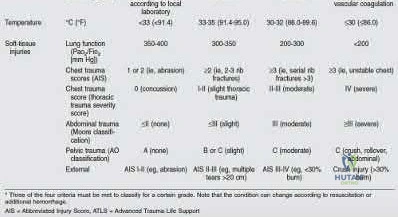

A 25-year-old male is brought to the trauma bay hemodynamically unstable following a motorcycle collision. Pelvic radiograph reveals an APC-III pelvic ring injury.

Despite application of a pelvic binder and initial fluid resuscitation, he remains hypotensive. What is the most common anatomical source of hemorrhage in this specific injury pattern?